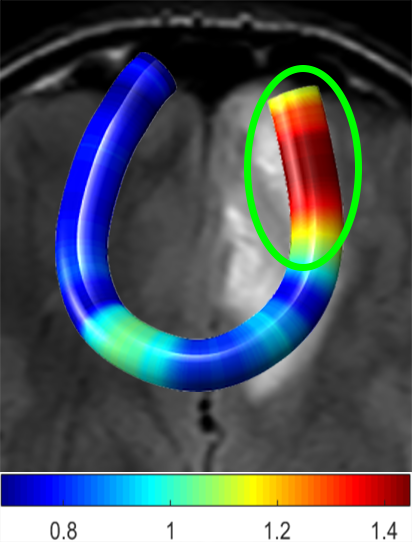

We performed pairwise comparison between two scans of a 32-year-old basketball player, diagnosed with mild occipital traumatic brain injury and frontal hemorrhage due to contrecoup impact, acquired one week and 6 months post-injury. The hemorrhagic lesion at the frontal right hemisphere of the player is no longer visible in the FLAIR image acquired 6 months after injury (Fig. 2a). Local differences between corresponding, longitudinal FA- and MD-FFDD profiles of the FMT (chosen due to its proximity to the lesion area) are shown in Fig. 2d. Figs. 2b-c present color-coded FMT to visually demonstrate these differences. Results show significant longitudinal variability at the right hemisphere part of the tract, corresponding to the lesion area, and relatively minor differences along the rest of the tract. These results should be considered as a proof of concept, validating the FFDD analysis results for the detection and localization of mTBI-related variabilities between fiber bundles.

| ONE WEEK | ![]() |

![]() |

FA-FFDD |

| 6 MONTHS | ![]() |

MD-FFDD |

| (a) FLAIR | (b) FA-FFDD | (c) MD-FFDD | (d) Local Differences |